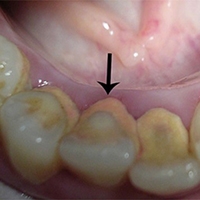

ปัจจัยความเสี่ยงของการเกิดโรคในช่องปาก

โรคในช่องปากที่เป็นที่รู้จักกันดี ก็คือ โรคฟันผุ เหงือกอักเสบ และโรคปริทันต์อักเสบ ซึ่งในคนที่เคย...

อ่านต่อ